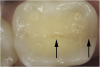

Fig 4. Subtle asymptomatic occlusal crack (arrow) of a mandibular right second molar (occlusal view).

Figure 4

Fig 5. Methylene blue dye staining further revealing the occlusal extent of the crack shown in Fig 4.